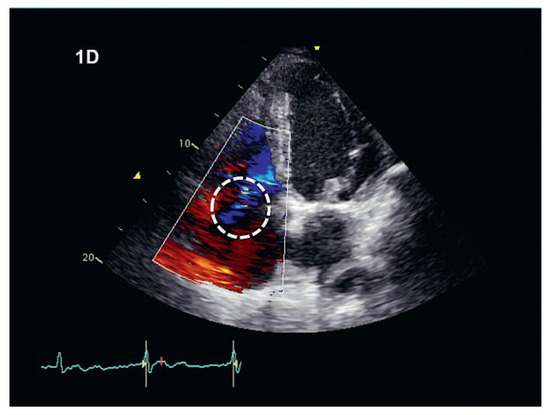

We report on the worldwide first implantation of a transcatheter valve in mitral position using a surgical approach to treat severe combined mitral valve disease, complicated by massive calcifications of the whole mitral anulus. The management of suc...